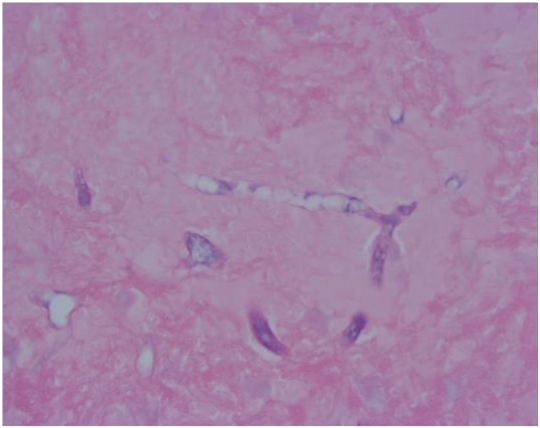

Histopathological examination with Gram stain (Figure 1) and Methenaminesilver stain (Figure 2 & 3) of thrombus revealed wide, non septate hyphae with right angle branching. Tissue biopsy showed necrosis, vasculitis, thrombosis and fungal vascular invasion suggesting mucormycosis. Amphotericin B was started and patient was transferred to another facility upon his request for limb amputation.

Figure 1 PAS.

Figure 2 Gomorimethenamine Silver Stain.

Figure 3 Gomorimethenamine Silver Stain.